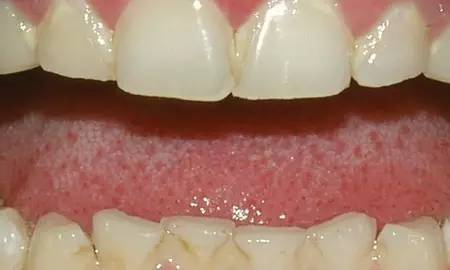

5、牙龈炎

牙龈炎是牙周病的最早阶段,是由牙菌斑引起的牙齿周围组织感染。如果患有牙龈炎,牙龈会变得红、肿、易出血,还可能会有口臭。牙周疾病通常是不痛的,很多人可能不知道自己患病。

如果偷懒不刷牙、不使用牙线、吸烟、牙齿不齐很难清洁、怀孕、有糖尿病或服用某些药物,则更可能患牙周病。在其早期阶段,牙周疾病是可逆的,牙龈可通过口腔医生的专业清洗、日常刷牙和使用牙线而恢复健康。